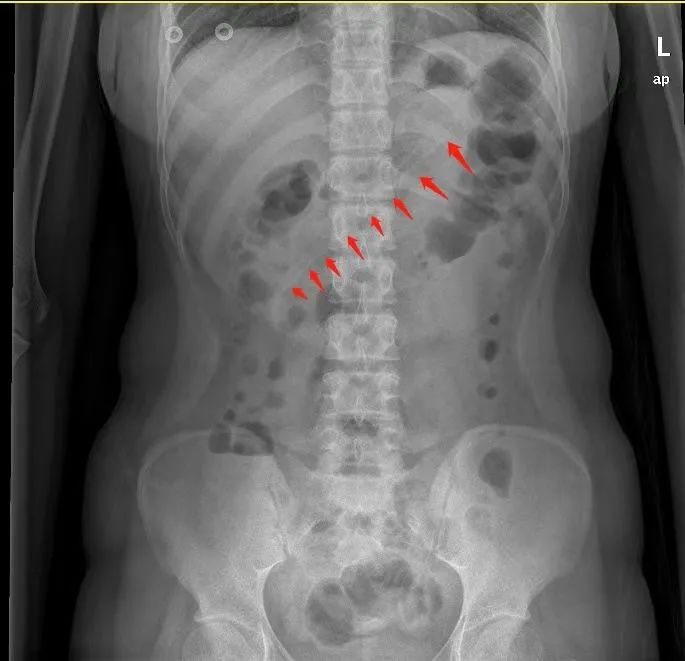

腹部X线检查显示,小李胃中的勺子长达17厘米,因此胃镜下取异物有较大的难度。但如果不取出,患者可能会出现消化道梗阻、出血和穿孔等并发症。因此,胃镜下取出异物势在必行。

术前,黄晓春主任进行了充分的术前告知后,患者及家属签字同意。与此同时,胃镜室与麻醉科也提前拟定了多个可能的方案,并知会耳鼻喉科和胃肠外科做好准备。术中,实施无痛麻醉后,在医生操作下,胃镜快速就位。通过胃镜,一进入胃腔就能看到一根长长的塑料勺子横跨在胃体至十二指肠球部。